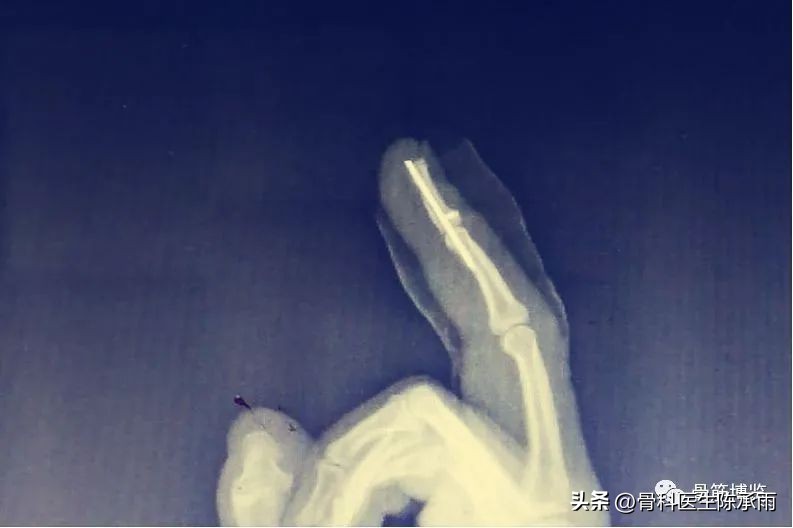

2、手术治疗

(1)经皮(不切口)背侧阻挡钉手术固定,缺点是仍有部分旋转不能矫正

(2)钢丝抽出指腹侧钮扣加克氏针固定或直接固定于克氏针上

(3)锚钉固定克氏针固定

一般固定6周后去除外固定或拔除克氏针及钢丝,逐步进行手指功能锻炼。